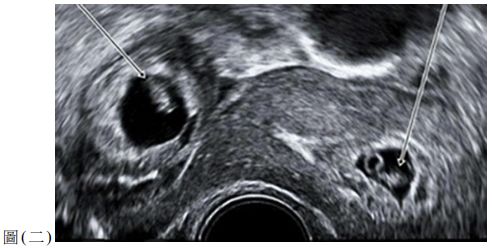

51. 42 歲婦女因為急性左腹痛及出血來急診。她主訴正在接受不孕症治療,且最近剛植入 三顆冷凍胚胎。尿液懷孕測試呈陽性。超音波檢查結果如圖 ( 二 ),也看到少量腹水。此 婦女最可能的診斷,下列何項較適當?

(A) 子宮角懷孕 ( cornual pregnancy ) (B) 間質懷孕 ( interstitial pregnancy ) (C) 子宮頸懷孕 ( cervical pregnancy ) (D) 異位懷孕 ( hete otopic pregnan y )